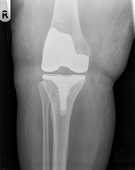

Knee replacement involves replacing the worn out knee joint. The end of the femur is resurfaced with a metallic component, a tray is placed on the tibia and a polyethylene spacer is inserted between the two components. For most total knee replacement the under surface of the kneecap is re-surfaced with a small polyethylene button.

In contrast to the hip joint the knee joint is made up of three parts or compartments. The inner (medial) and outer (lateral) halves and the patello-femoral joint (knee cap), it is possible to replace these separate components in isolation, depending of the type and pattern of arthritis the patient has.